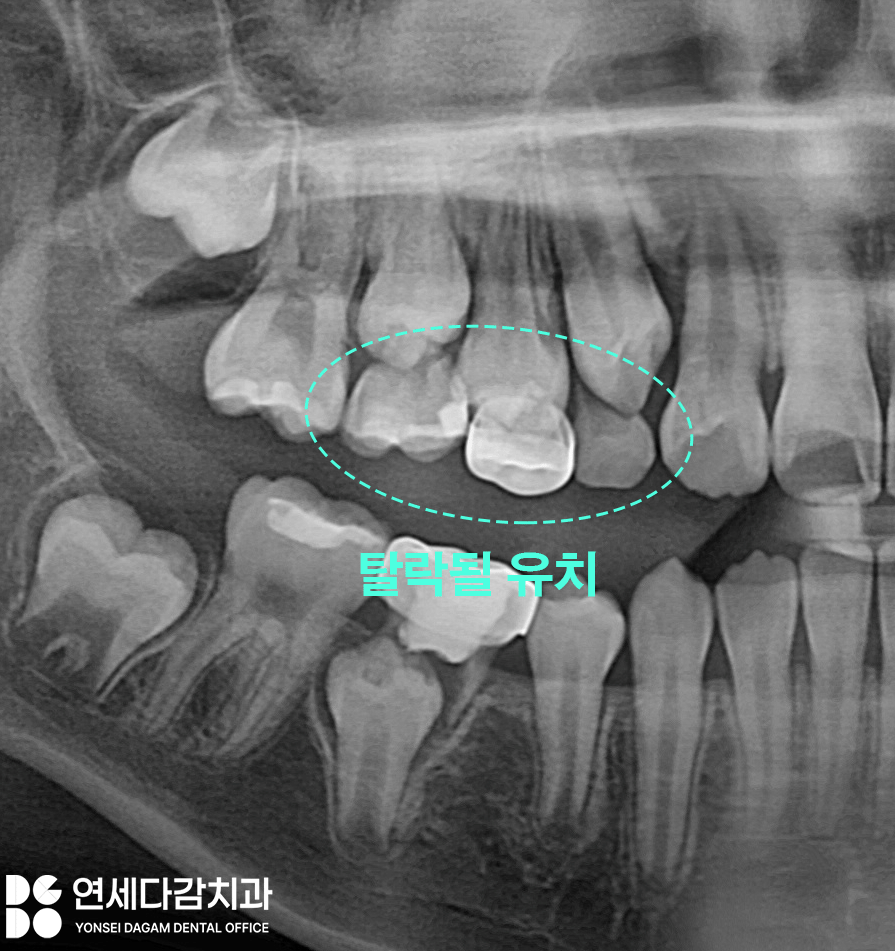

엑스레이 사진을 촬영해 봤을 때

탈락될 유치 밑으로

교체될 영구치가 올라오는 것이

보이는 게 정상입니다.

그러나 잇몸뼈 속에 있어야 할

영구치가 보이지 않는 경우,

선천적 영구치 결손이라 판단합니다.